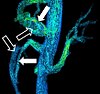

| Diffusion tensor | DTI | Mainly tractography (pictured) by an overall greater Brownian motion of water molecules in the directions of nerve fibers.[70] |

|

| |